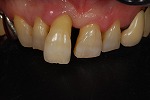

歯をより白く綺麗にしたいと思う方々は多いと思います。審美歯科とは、白い歯が見える口元だけではなく、機能的で歯周組織と顔貌に調和した自然美を追求する治療です。治療は短期間(歯冠修復・ホワイトニングなど)で終わるものから長期に渡る全顎的な治療(歯周病治療・矯正治療・インプラント治療など伴うケース)を行う症例もあります。当院での歯冠修復は

- ジルコニアクラウン修復

- メタルボンドクラウン修復

- グラスセラミッククラウン修復

- ハイブリットインレー、アンレー修復

- コンポジットレジン充填

等の歯冠修復を行っています。

◆コンポジット充填

→